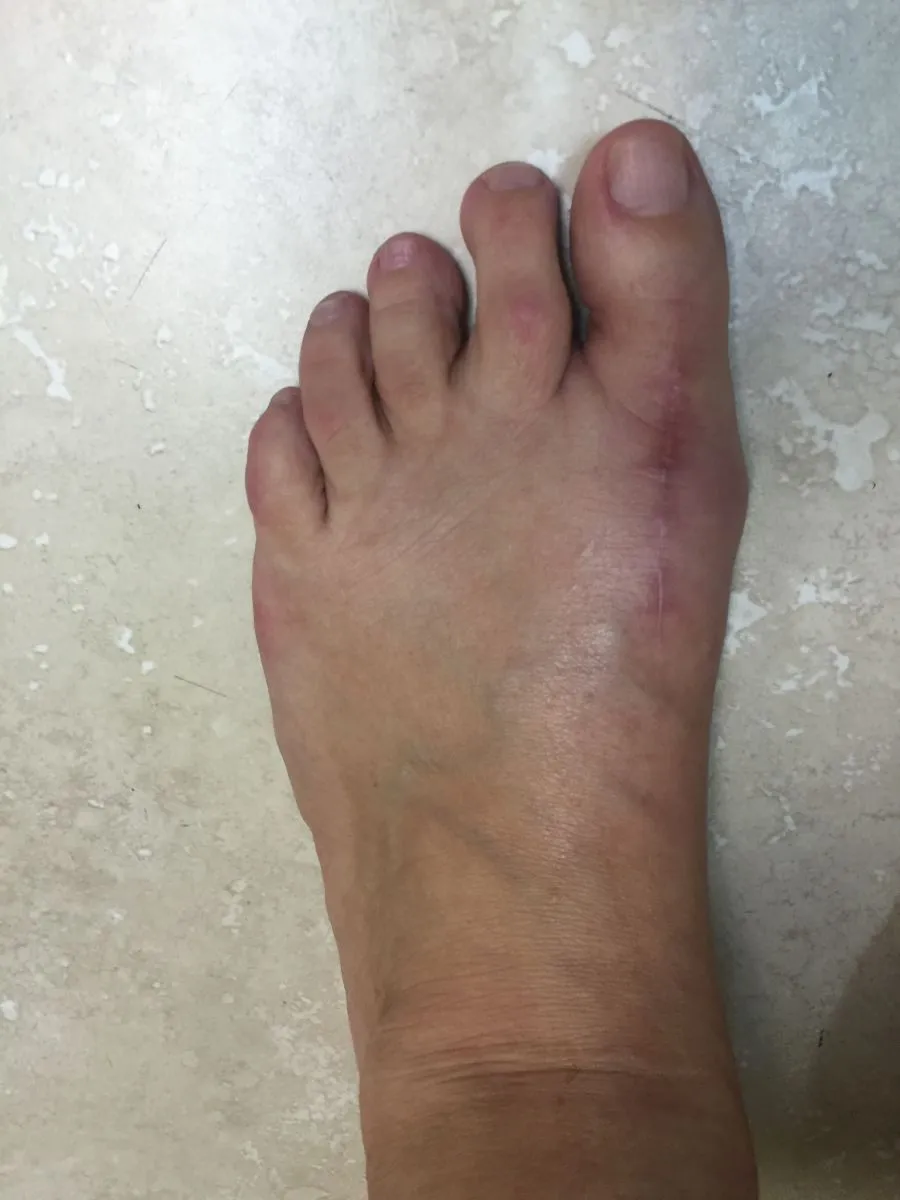

Before and immediately postop S/P bunionectomy

Before and 6 months status post bunionectomy.